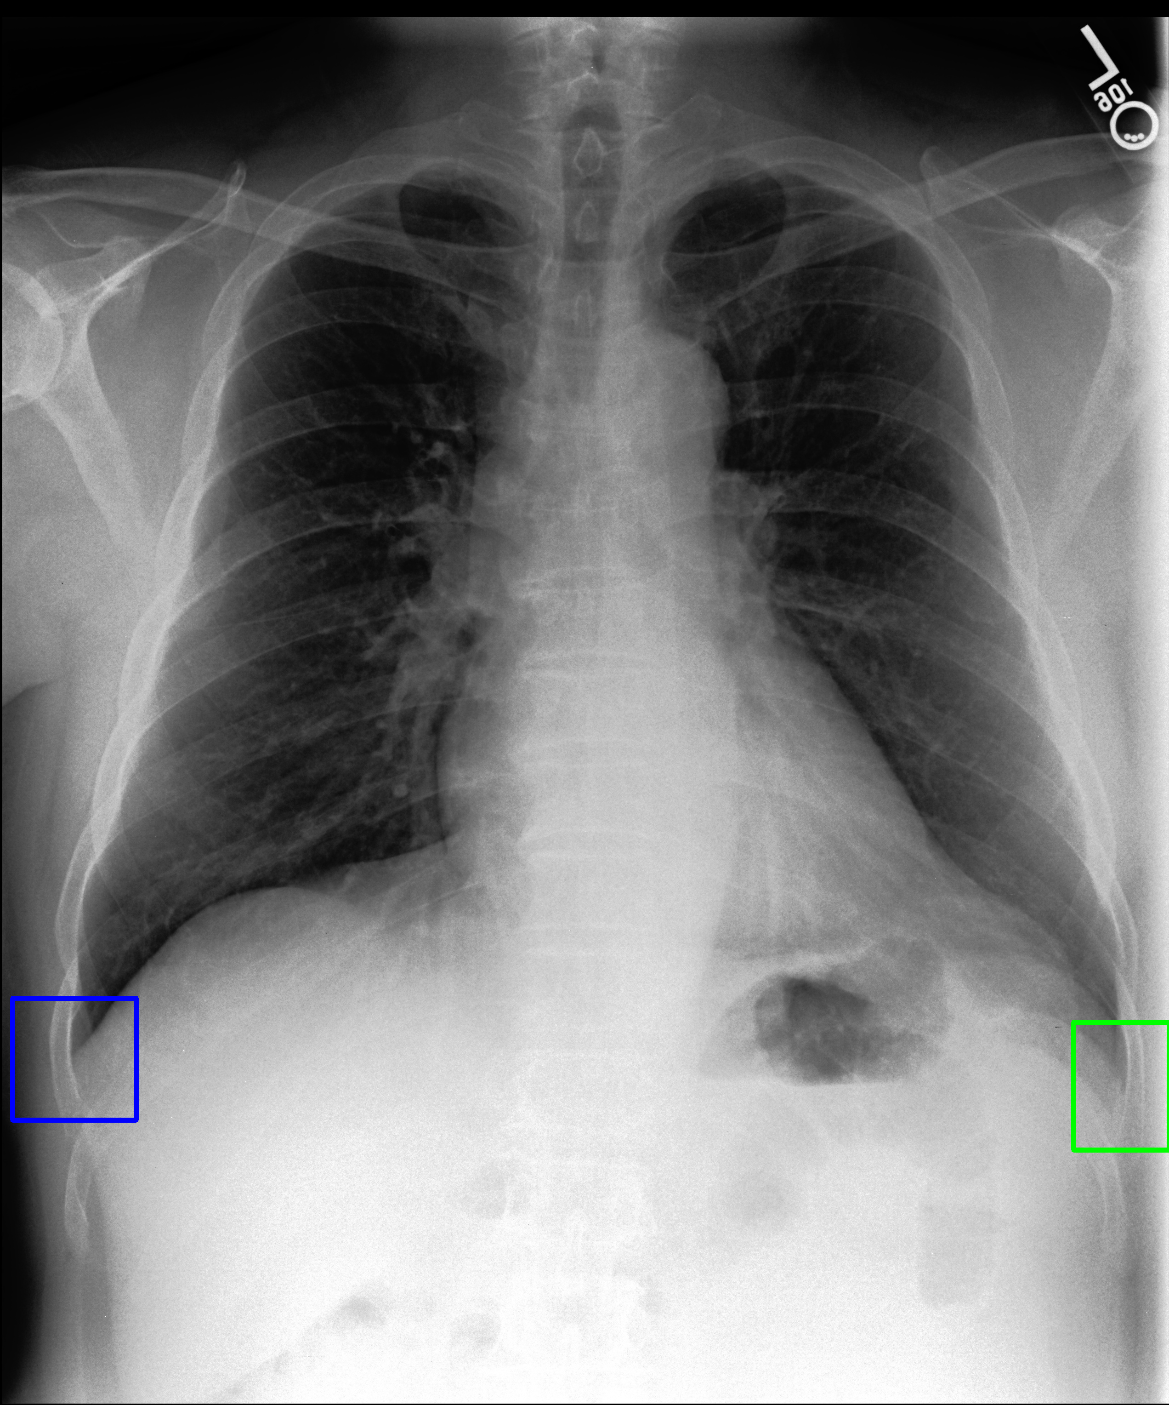

In Figure 3 we also visualize the output of Grad-CAM [20] method on the GlobalView model to highlight the importance of the localization, while the prediction of Enlarged Cardiac Silhouette was correct, the GlobalView model was focused on the lungs. Our method was able to provide accurate localization information as well as the finding.

Refer to caption

(a)

(b)

(c)

Figure 3: An example image from our dataset with enlarged cardiac silhouette. The GlobalView network detects this label correctly, but as the Grad-CAM activation map shows (b), the attention of the network is not on the cardiac region. Our method detects the finding in the correct bounding box (c).

This approach accurately detects any of the nine studied abnormalities and places it in the correct bounding box in the image. The 18 pre-specified bounding boxes are devised to map to the anatomical areas often described by radiologists in chest X-ray reports. As a result, our method provides all the necessary components for composing a structured report. Our vision is that the output of our trained model, subject to expansion of the number and variety of findings, will provide both the finding and the anatomical location information for both downstream report generation and other reasoning tasks. Despite the difficulty of localized disease detection, our method outperforms a global classifier. As our data shows (See Figure 3), global classification can be unreliable even when the label is correct as the classifier might find the correct label for the wrong reason at an irrelevant spot.